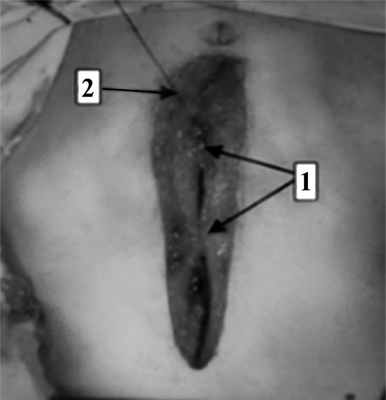

Способ моделирования заключается в следующем: Отступя 2 см от края раны в направлении сверху-вниз скальпелем производят насечки на коже длиной 4-5 мм каждые 4 сантиметра сначала с одной стороны, а затем аналогичные симметричные разрезы кожи с противоположной стороны (Фиг.1). Заготавливают необходимое количество трубок из поливинилхлорида (ПВХ) диаметром 4 мм и длиной 15 см. Далее 5 мм троакаром формируют канал, прободающий кожу (1), подкожную клетчатку (2), передний листок апоневроза прямой мышцы, прямую мышцу (3), задний листок. Сразу же достигнув заднего листка выкол троакара производят в косом тангенциальном направлении к ране так, чтобы он оказался в предбрюшиной клетчатке (4) и не задел брюшину (5) (Фиг. 2). Конец трубки берут рукой и подводят к ране. Затем в сформированный канал вводят зажим Кохера, захватывают конец подведенной трубки и выводят её наружу. Аналогичным образом формируют канал на противоположной стороне и второй конец ПВХ-трубки проводят на кожу. Свободные концы трубок захватывают в зажим. Манипуляцию повторяют до тех пор, пока вся рана не будет взята на ПВХ-трубки (Фиг. 3). Далее ассистент берет концы трубок и стягивает края раны до сопоставления, тут же фиксируя концы трубок зажимом Микулича (Фиг. 4). Сразу же под зажимом трубки связываются плетеной нитью (Фиг. 5). Количество швов на трубках из поливинилхлорида может быть вариабельным в зависимости от длины лапаротомной раны, толщины брюшной стенки, выраженности воспалительного процесса в ране. Между полученными швами накладываются редкие швы Донати с целью возможной последующей ревизии раны. С целью профилактики некрозов кожи под трубчатые швы подкладываются марлевые салфетки (Фиг. 6). Швы Донати и трубки рекомендуем снимать на 10-е сутки.

На следующем этапе, после проведения обучения, новый способ лапарорафии внедрили в клиническую практику (рис. 3). Рис. 3. Ушивание лапаротомной раны (интраоперационная фотография). 1 — наложены укрепляющие швы; 2 — наложение непрерывного шахматного шва.